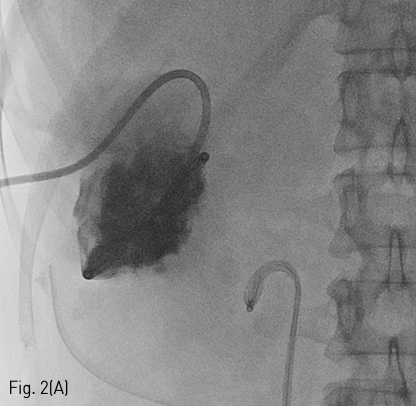

Fig 2A

(A) Spot radiograph shows percutaneous drainage catheter in the urinoma cavity.